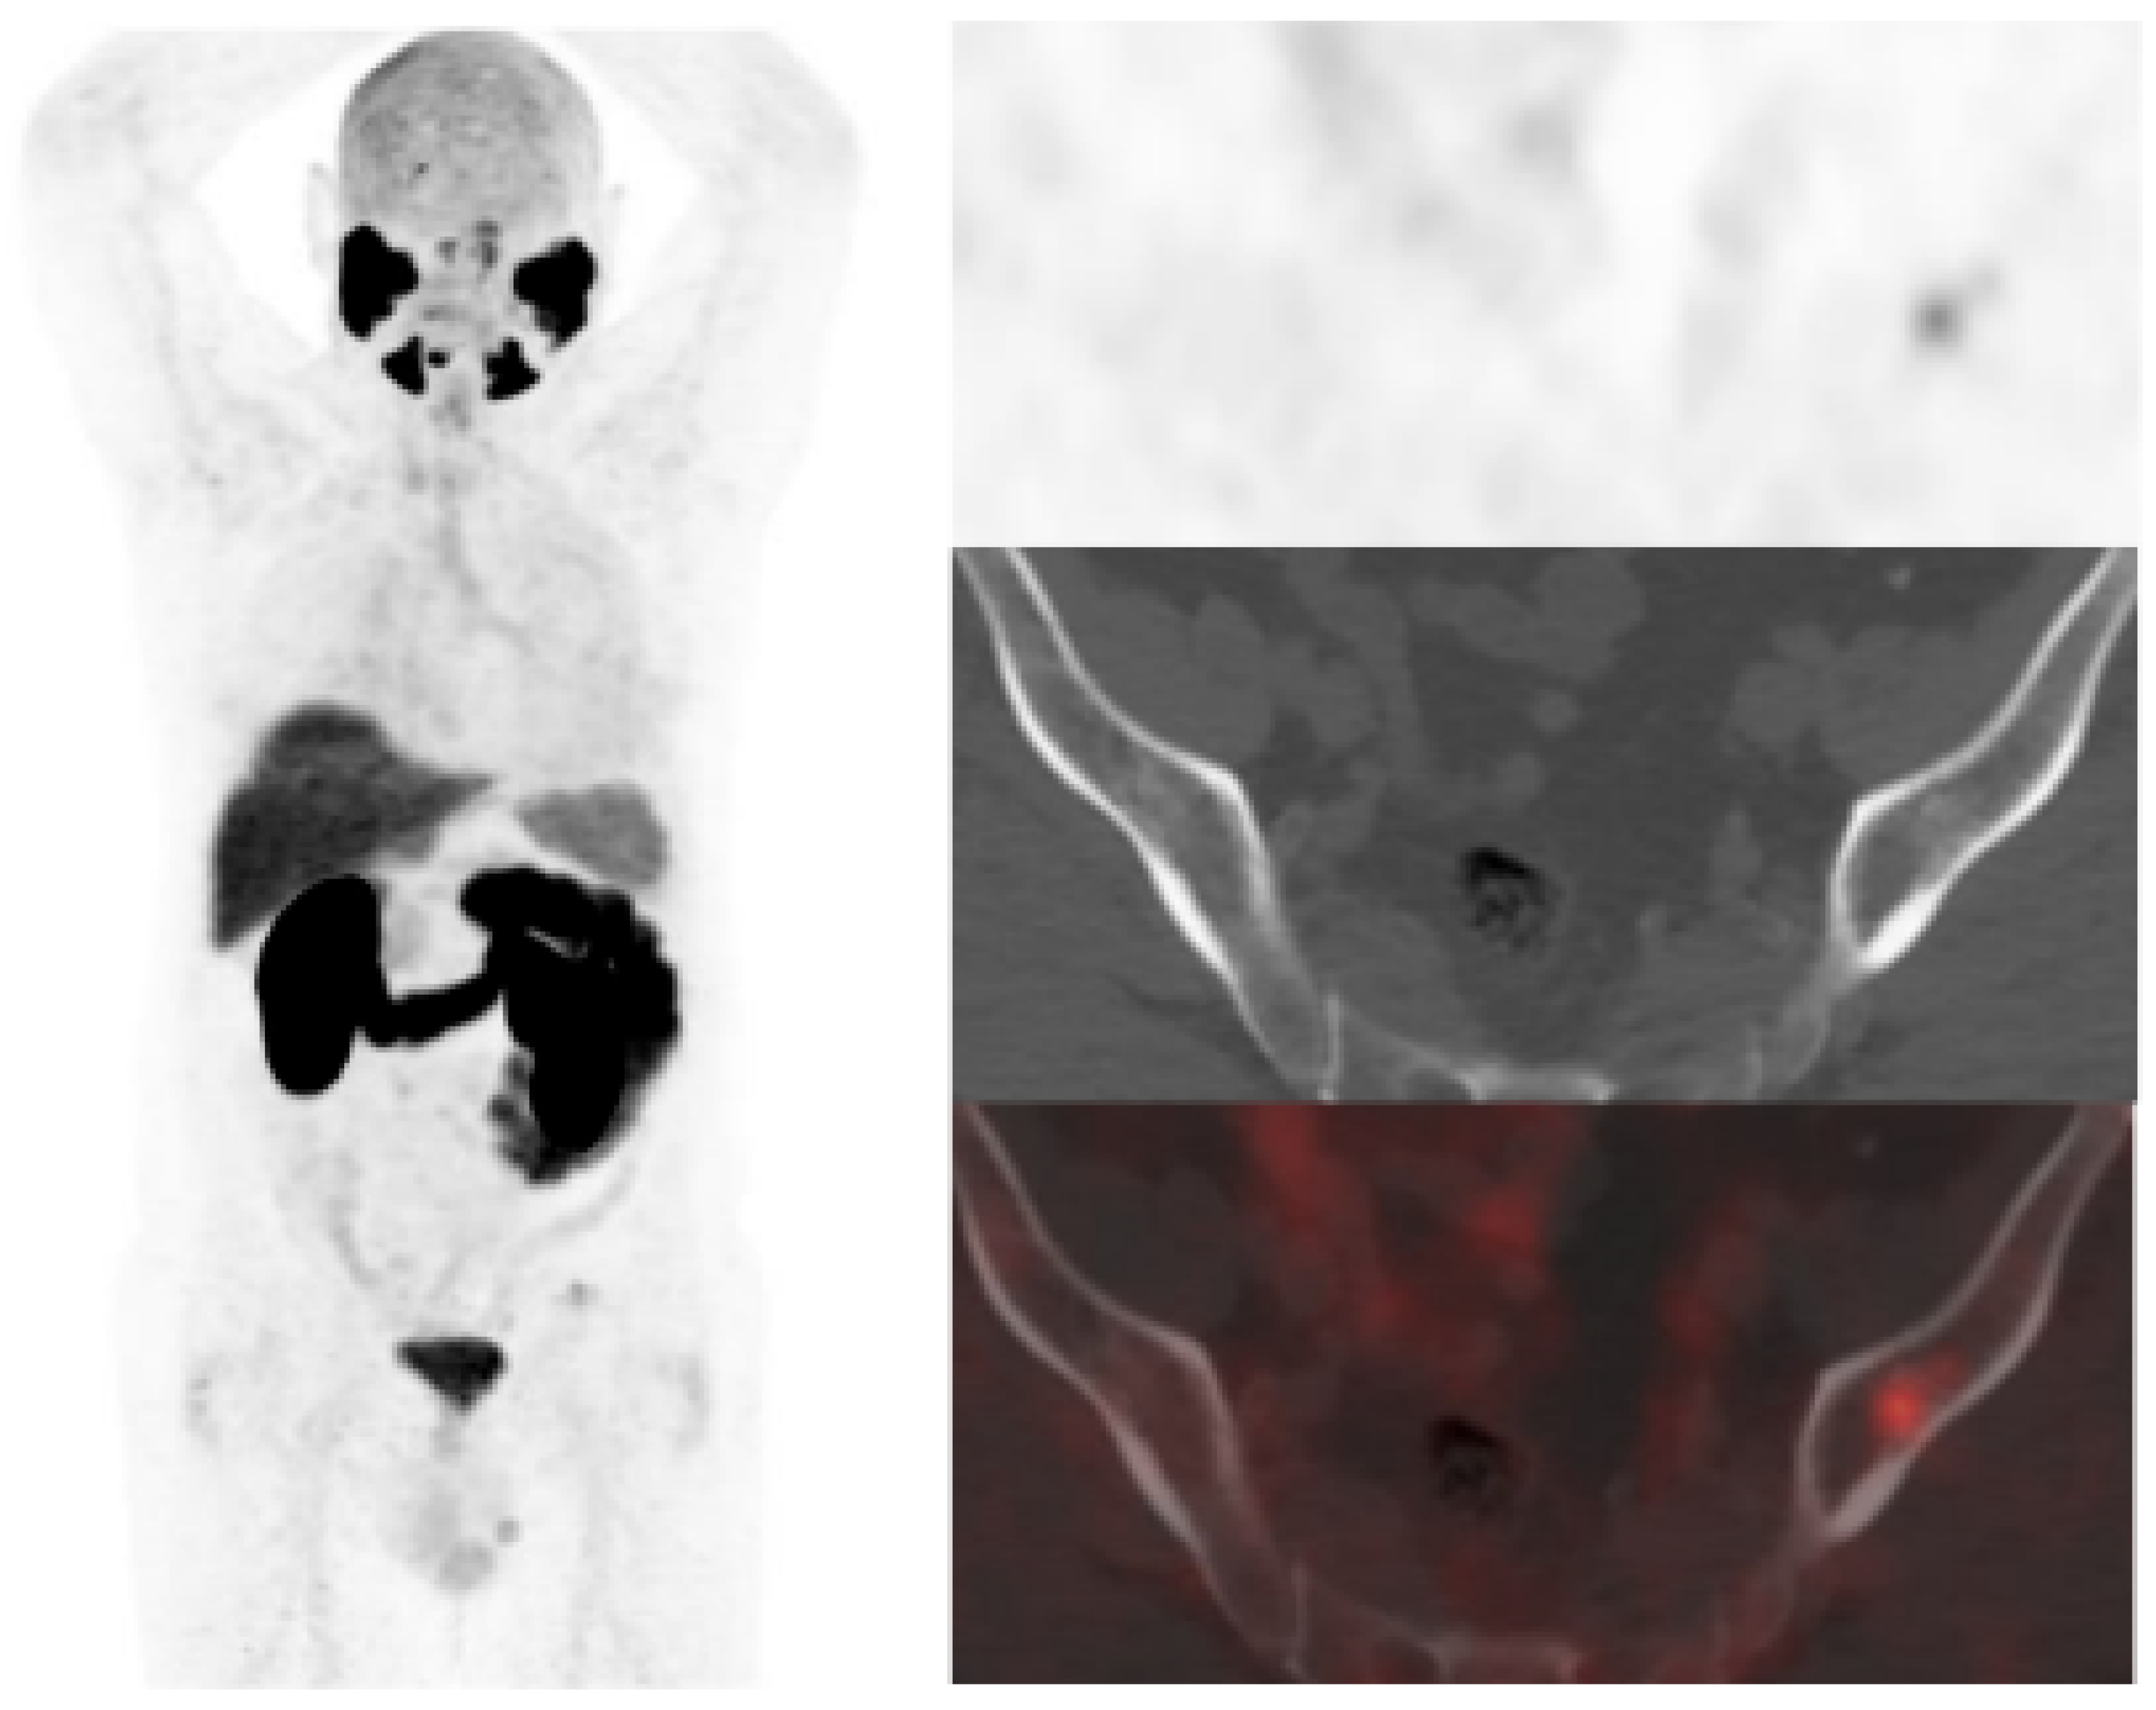

[18F]DCFPyL-PET/CT was negative in 49/138 patients (7 low, 14 intermediate and 28 high risk). Follow-up without active treatment was adopted in 29 patients (4 positive [18F]F-choline-PET/CT) and 20 intermediate/high risk patients underwent treatment (12 prostatic fossa radiotherapy, 8 ADT, 1/8 [18F]F-choline-PET/CT positive). Regarding the false positive, six patients with positive [18F]DCFPyL-PET/CT (2 prostate gland, 3 bone and 1 rectum) had a normal MRI (Figure 5 and Figure 6). Ten patients were [18F]F-choline-PET/CT positive and considered false positive (2 prostate gland, 5 lymph nodes, 2 bone, 1 pelvic mass) due to [18F]DCFPyL-PET/CT result, biopsy or clinical follow-up.

Figure 5.

BCR in a 71-year-old patient (PSA: 0.26 ng/mL, PSAdt: 1.09 months, PSAvel: 0.2 ng/mL/month) after RP of PCa (Gleason 6, pT2c). [18F]DCFPyL scan showed a slight uptake on left iliac bone with minimal sclerotic changes. Previous negative [18F]F-choline scan (time window of one week). MRI did not confirm malignancy of PSMA uptake (false positive). Prostatic bed radiotherapy was given and PSA level decreased.